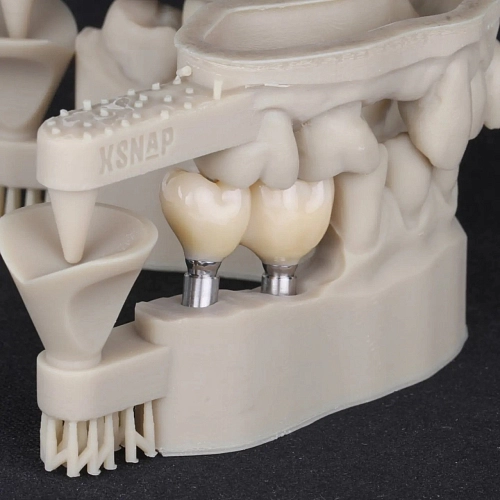

На фото представлен клинический случай.

Протезирование на имплантах с подготовкой костной ткани и десны в позиции зубов 47,47